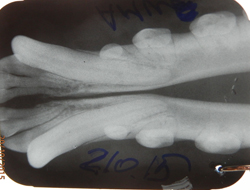

Во время чистки зубов, особенно у мелких пород собак, врач становиться перед выбором удаления зубов. А именно,в их количестве. Иногда это 3-5, в тяжелых случаях 7-10штук. Эта цифра пугающая для владельца. То есть владелец задает вопрос:- « Зачем так много». А ведь действительно, когда мы начали делать снимки проблемных зубов. Выяснили:что около 25% зубов проблемного ряда можно оставить на месте, у них еще есть минимальный запас корня и его лунки.

Стала доступна возможность пломбировки зубных каналов. Стал качественней процесс пломбировки корней зубов,чего ранее, в городе Днепропетровск не проводилось.